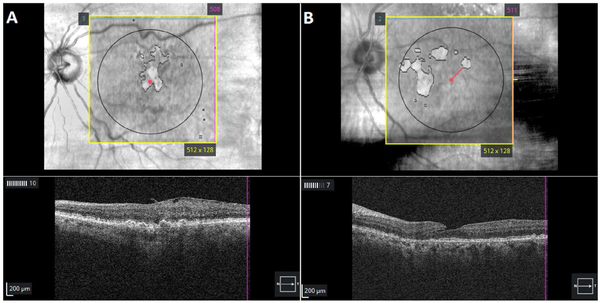

Figure 1

Optical coherence tomography of automated subretinal pigment epithelium illumination showing outlines of (A) a fovea-involving lesion with geographic atrophy (GA) and (B) an extrafoveal GA lesion in patients diagnosed with intermediate age-related macular degeneration.